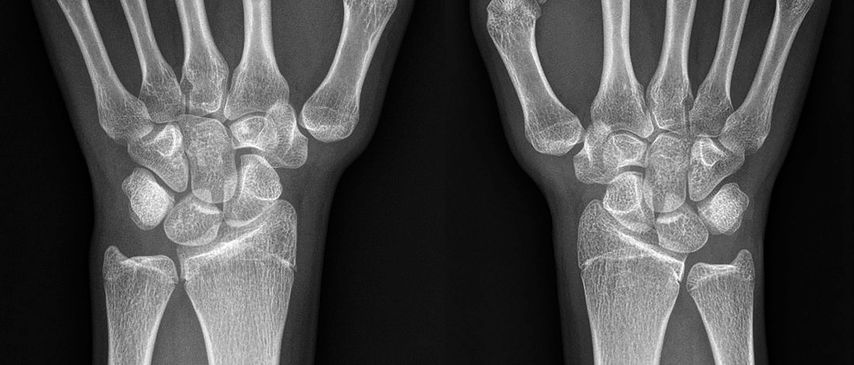

Abb. 2: Röntgen (Handgelenk a.p.) einer jungen erwachsenen Patientin mit manifester Rhizarthrose und Hypoplasie des Os trapezium beidseits. Der verminderte Gelenksabstand und die veränderte Basis des ersten Metacarpale links sind eindeutig ersichtlich (Eaton-Littler-Grad II). Rechts liegt ein verbreiterter Gelenksspalt entsprechend Grad I vor13

Chronische Instabilitäten, hervorgerufen durch habituelle Bandlaxizität, führen zu einem vermehrten Stress auf ligamentäre Strukturen an der Basis des ersten Metakarpalknochens und zu Gelenksfehlstellungen. Als Folge kommt es zu einer vermehrten Arthrose der betroffenen Gelenke (siehe Abb. 2 und Abb. 3). Diese Veränderungen gehen mit einer erheblichen Morbidität einher und betreffen vor allem postmenopausale Frauen.12 Nach Eaton und Littler wird die Arthrose des Daumensattelgelenkes in 4 Schweregrade eingeteilt.13 Der Schweregrad und die funktionellen Einschränkungen des CMC1-Gelenkes sind mitunter entscheidend bei der chirurgischen Indikationsstellung und machen den Großteil rekonstruktiver Eingriffe aus.5